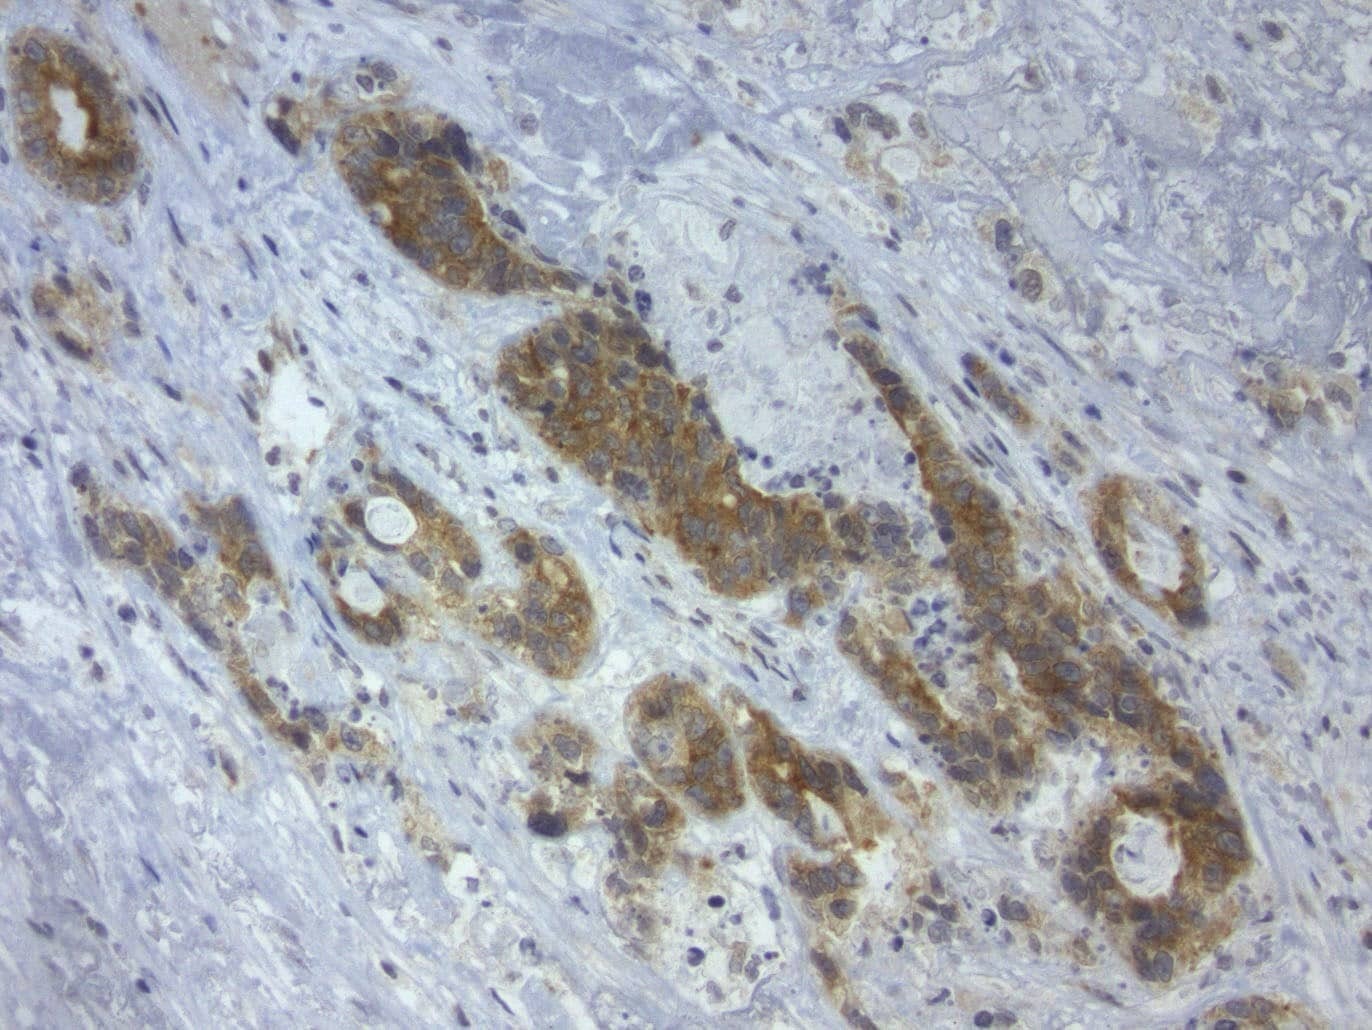

- Immunohistochemical staining of paraffin-embedded Adenocarcinoma of Human colon tissue using anti-LGR5 mouse monoclonal antibody. (Heat-induced epitope retrieval by 1mM EDTA in 10mM Tris buffer (pH8.5) at 110°C for 10 min, UM800104)(1:150)